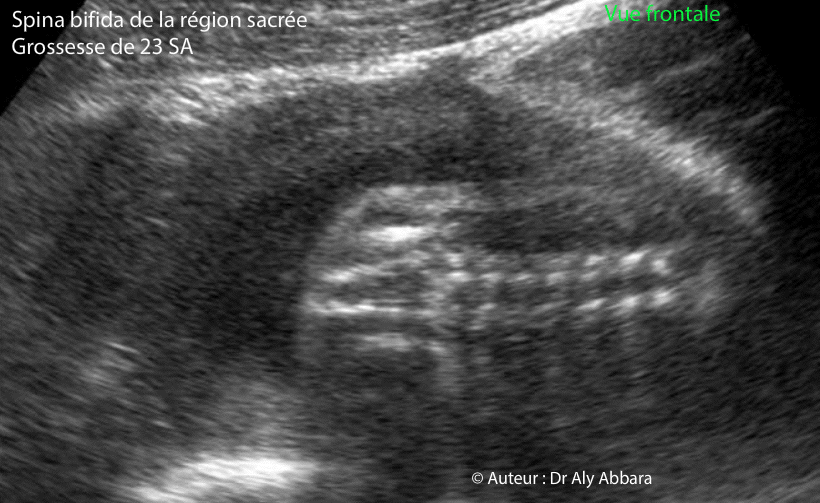

Images échographiques montrant un spina bifida aperta (non fermeture du tube neural) de la région sacrée avec petite méningocèle. Il s'agit de coupes frontales montrant la solution de continuité au niveau des arcs postérieurs des vertèbres avec absence des processus épineux (qui sont bien identifiables au niveau des vertèbres lombaires) ; puis sur ces images on peut aussi individualiser une petite méningocèle située au niveau des premières vertèbres sacrées. Cette non fermeture du tube neural a été mise en évidence chez un fœtus trisomique 13 âgé de 23 SA. D'autres malformations majeures ont été mises en évidence : séquence holoprosencéphalie alobaire avec microcéphalie (périmètre céphalique = 170 mm, soit "-3,24 DS") proboscis, cyclopie, arhinie ; hypoplasie du pavillon de l'oreille externe ; un foyer échogène intra-cardiaque ; une artère ombilicale unique ; puis une hyperéchogénicité intestinale ; main crispée unilatérale et enfin, un retard de croissance in utero modéré et symétrique. |